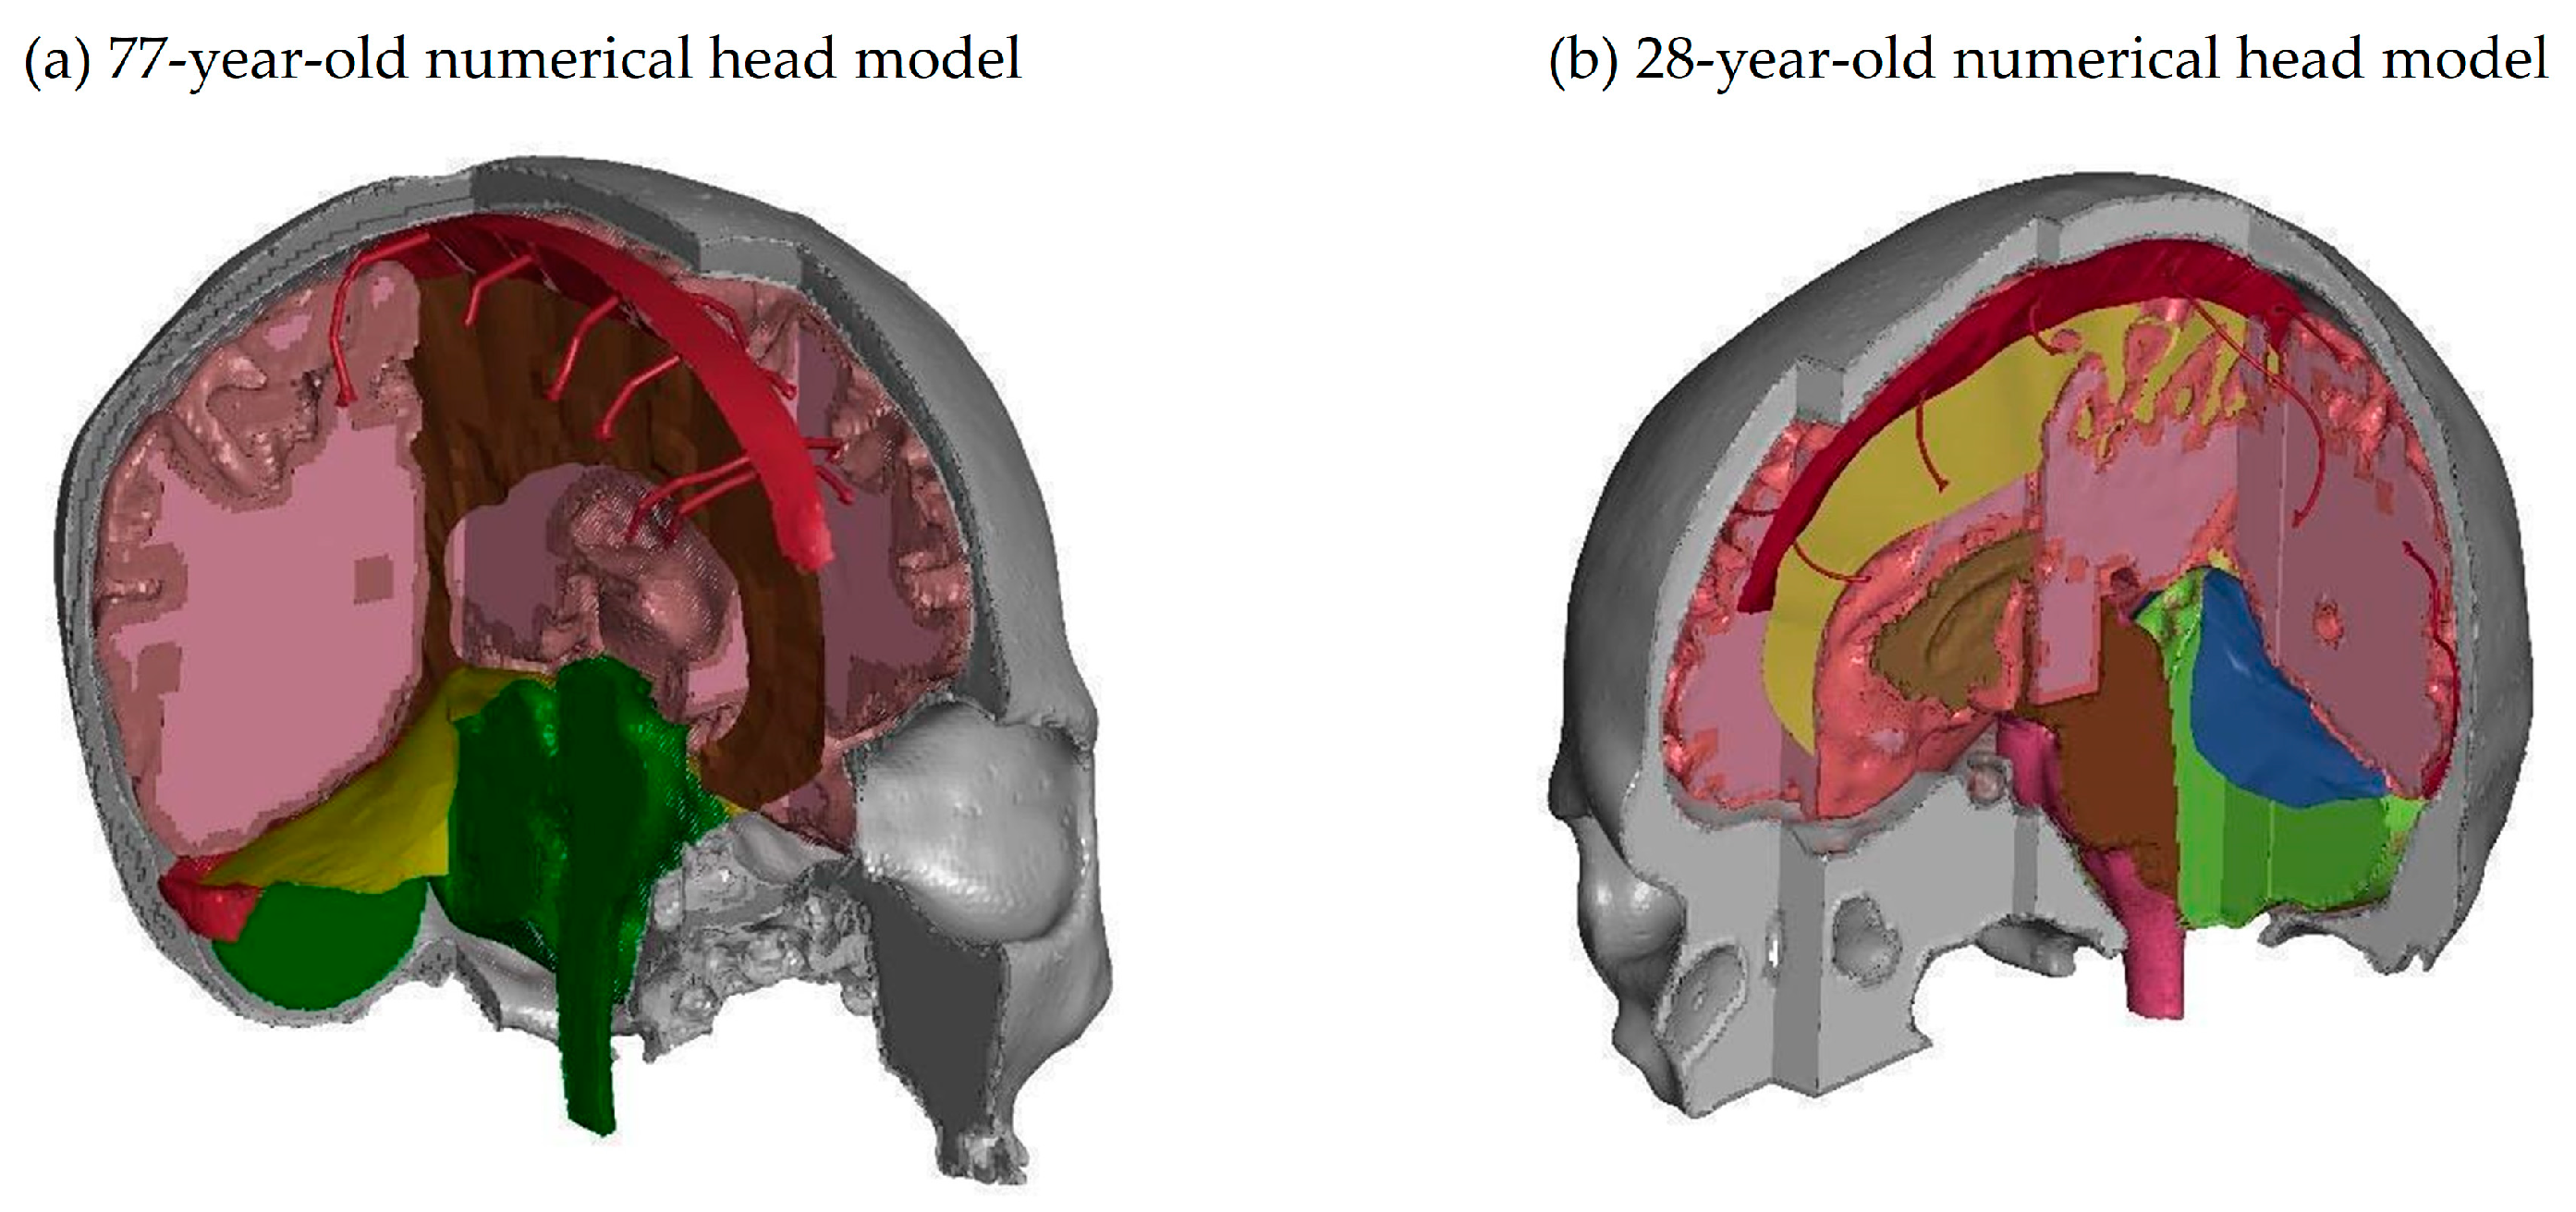

2.2. Development of the Human Head Numerical Model

2.3. Model Geometry

Brain Physical Differences

| Brain Parameters (White and Grey Matter) | Young Adults (28 y)  | Senior (77 y) | Difference (Young Adult vs. Senior) | Comments |

|---|---|---|---|---|

| Brain Volume | 1.0406 [dm3] | 0.98088 [dm3] | 5.7% | Young Adults: On average, young adults tend to have larger brain volumes compared to older adults, with a ~6% difference. This is largely due to ongoing brain development and growth during childhood and adolescence [40]. Senior Adults: Brain volume typically decreases with age. This reduction can be attributed to factors such as loss of neurons and their connections, as well as changes in brain structural integrity. This decrease in volume can affect various cognitive functions. |

| Brain Area | 165,893.3 [mm3] | 1,619,62.1 [mm2] | 2.4% | Young Adults: Younger individuals generally have a larger brain area compared to older adults, with a ~2% difference. The brain area encompasses the surface of the brain, which is important for processing information and facilitating communication between different brain regions. Senior Adults: Over time, there may be a slight reduction in the brain’s surface area. This could be related to the gradual decline in cognitive functions, such as memory and processing speed, experienced by some older individuals. |

| Brain Mass | 1.18 [kg] | 1.02 [kg] | 13.3% | Young Adults: Young adults typically have greater brain mass compared to older adults, with a ~13% difference. Brain mass is closely related to brain volume and is largely responsible for the organ’s overall functionality. Senior Adults: As individuals age, there is often a decline in brain mass, primarily due to a decrease in the number of neurons and synaptic connections. This mass reduction can contribute to age-related cognitive decline. |